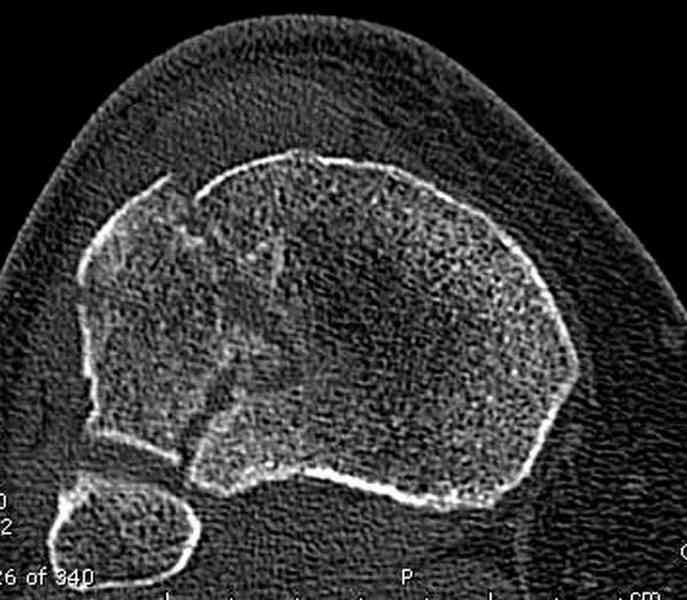

Касаемо перелома мыщелка, лучше сделать СКТ и после определиться с операцией. Фиксировать - проксимальной поддерживающей пластиной. Есть хорошие варианты. Чтож до дистальной части - аппарат кроме стабилизации ничего не даст. Если 6 кг вытяжения не расколотили отломки, то при открытом доступе вся эта мелочь вывалится. По-моема операцию следует рассматривать с позиции подготовки к артродезу (ось выправить, осколки попытаться собрать). Ну и готовить морально пациентку к неработающему голеностопу.

Для внутрисуставных переломов необходимо идеальное сопоставление, а такая задача без КТ срезов усложнится. Только КТ надо делать после дистракции сустава, иначе нельзя получить объективную информацию.

Пациентки прооперирована, результат чего на снимках. Выполнена открытая репозиция костей правой голени, синтез малоберцевой пластиной, б/берцевой винтами, имеющиеся фиксаторы не подходили, было принято решение репонировать отломки, синтез винтами, гипсовая повязка.

В данный момент локально отёк тыла стопы незначительный, двигательня функция сохранена, ограничена болевым синдромом. Пульсация артерий ослаблена, соответствует левой ноге. Рана - в области границы с пузырём область некроза 2.5*2 см, сухой, не увеличивается, под ним чувствительность сохранена. Чувствительность по всей поверхности кожи в норме, гипоестезия пальцев, при чём варьирует от нормальной, до почти анестезии в течении дня.

Репозиция внутрисуставных переломов неудовлетворительная и не адекватна.

сценарий и для перелома наружного мыщелка б.б.- передний фрагмент стоит на месте, а задний не репонирован - в таком положении оставлять фрагменты нельзя, суставная поверхность должна быть реконструирована.

При наличии менее агрессивных методов (аппарат) попытка под любым предлогом установить “из того что было в наличии”, и тем более при отсутствии показаний, не считается "благородным делом". Упрямство в лечении внутрисуставных переломов не в интересах больного, и привело к неудовлетворительной фиксации.

В лечении переломов пилона восстановление длины малоберцовой является индикатором и ориентиром для успешного лечения. Первый этап восстановления по длине не удался, малоберцовая остается короткой, и репозиция суставной поверхности осталась неудовлетворительной. Длина передней колонны не восстановлена, а в дистальном фрагменте имеется флексия. Оставлена без внимания потеря кости в метафизе. Шурупы 4.5 мм будут выступать после спадения отека, и возможно будут причиной мягкотканого осложнения в гипсе.